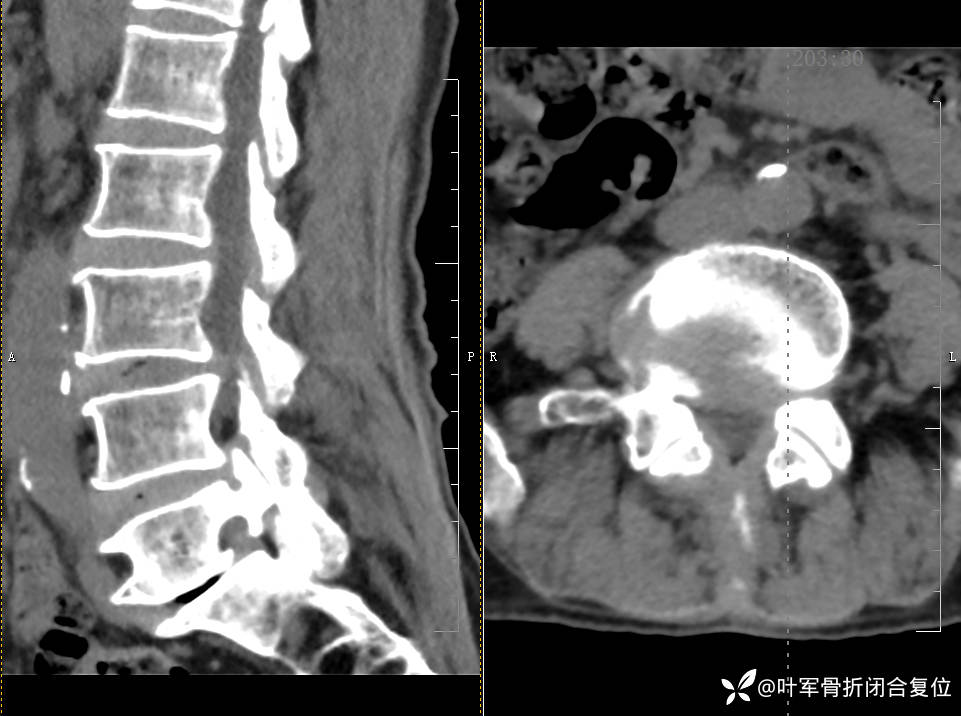

腰椎MR提示腰椎退行性改变、椎间盘膨出、腰5双侧椎弓峡部裂伴椎体轻度向前滑脱。

1. 腰椎滑脱: 腰5双侧椎弓峡部裂伴椎体轻度向前滑脱可导致腰椎不稳,压迫神经根及马尾神经,产生相应症状。

2. 腰椎椎管狭窄: 椎管狭窄可压迫脊髓神经根,引起下肢麻木、疼痛和间歇性跛行。

3. 影像学检查:若影像学检查(如MRI、CT)显示明显的椎管狭窄、椎体滑脱等病理改变且与临床症状一致,手术可能是必要的选择。